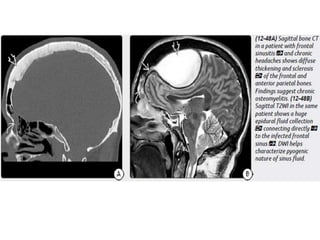

extension of infection from paranasal sinus disease.

Approximately 20% of empyemas in older children and adultsare

secondary to otomastoiditis.

Imaging

NECT scans may be normal or show a hypodense extraaxial collection

that demonstrates peripheral enhancement on CECT.

Bone CT should be evaluated for signs of sinusitis and otomastoiditis.